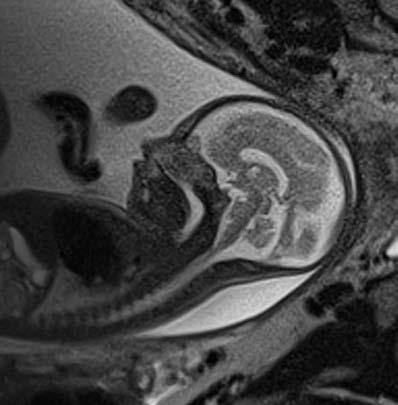

When an unborn baby has an abnormality, decisions about the delivery and neonatal care can often be planned in advance – with the help of an MRI.

MRI image acquisition can be tricky and quality reporting is an acquired skill. An expert in the field, Dr Lauren Raubenheimer honed her skills in London under world-renowned foetal and neonatal imaging specialist, Prof Mary Rutherford. Dr Raubenheimer joined SCP Radiology as a consulting radiologist.

As a mother herself, Dr Raubenheimer has a deep emotional investment in her work.

“When a couple discovers their baby has an abnormality, the impact is enormous,” she explains. “I hope my findings give parents more answers as they navigate a difficult path.” With the help of an MRI, Dr Raubenheimer says that in many cases, the timing and route of delivery, as well as the neonatal care required, can be planned in advance.

When would Foetal MRI be recommended?

Patients are typically referred from Foetal Medicine

Specialists after an abnormality has been detected on a screening ultrasound. An MRI can be done to confirm the abnormality, as well as to assess for abnormalities that are not readily visible through standard imaging techniques. This can significantly affect the prognosis. A foetal MRI can be performed either in the second or third trimester.

Dr Raubenheimer’s special interest is in developmental foetal brain abnormalities, but she also performs MRIs for body abnormalities, including congenital diaphragmatic hernia and spina bifida.

MRI can be superior to ultrasound in certain instances, such as assessing the folding of the brain and parts of the brain obscured by the skull, when amniotic fluid is low and when mothers have a high body mass index (BMI).

Foetal movement used to be an obstacle in getting good quality MR images. However, with today’s advanced magnets and faster imaging sequences, excellent image quality can be obtained. At SCP Radiology, foetal MRI scans are done exclusively by lead MRI radiographer Andrea Nagel.

comes

Safety is, of course, of utmost importance. Dr Raubenheimer reassures us that present data shows no conclusively documented harmful effects of MRI imaging on the

developing foetus, providing it is at the safe and optimal level. She also adds that MRI does not use ionising radiation, and intravenous contrast is not administered in foetal MRI.

Foetal MRI is covered by medical aids, but pre-authorisation is required.

Dr Raubenheimer prefers that patients are referred from a Foetal Medicine Specialist after a detailed ultrasound. “Having access to ultrasound reports and knowing the exact gestation is crucial to an accurate MRI report,” she emphasises.